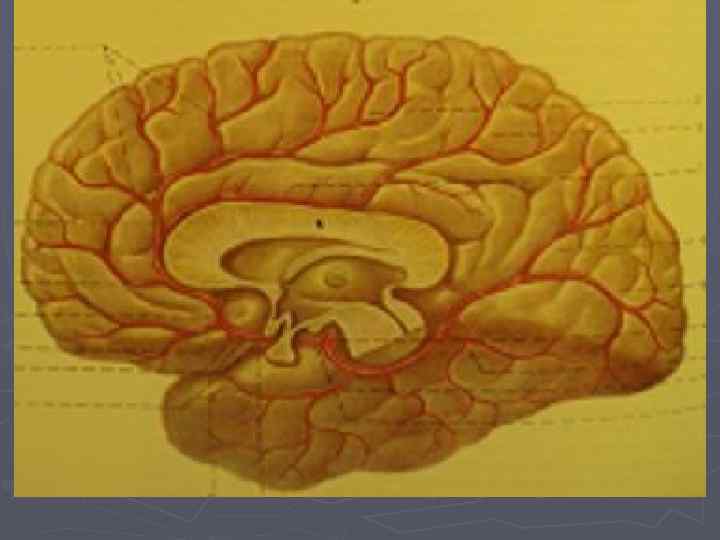

Кровообращение головного мозга

Зоны кровоснабжения артериями ► Передняя мозговая артерия ► Средняя мозговая артерия ► Задняя мозговая артерия